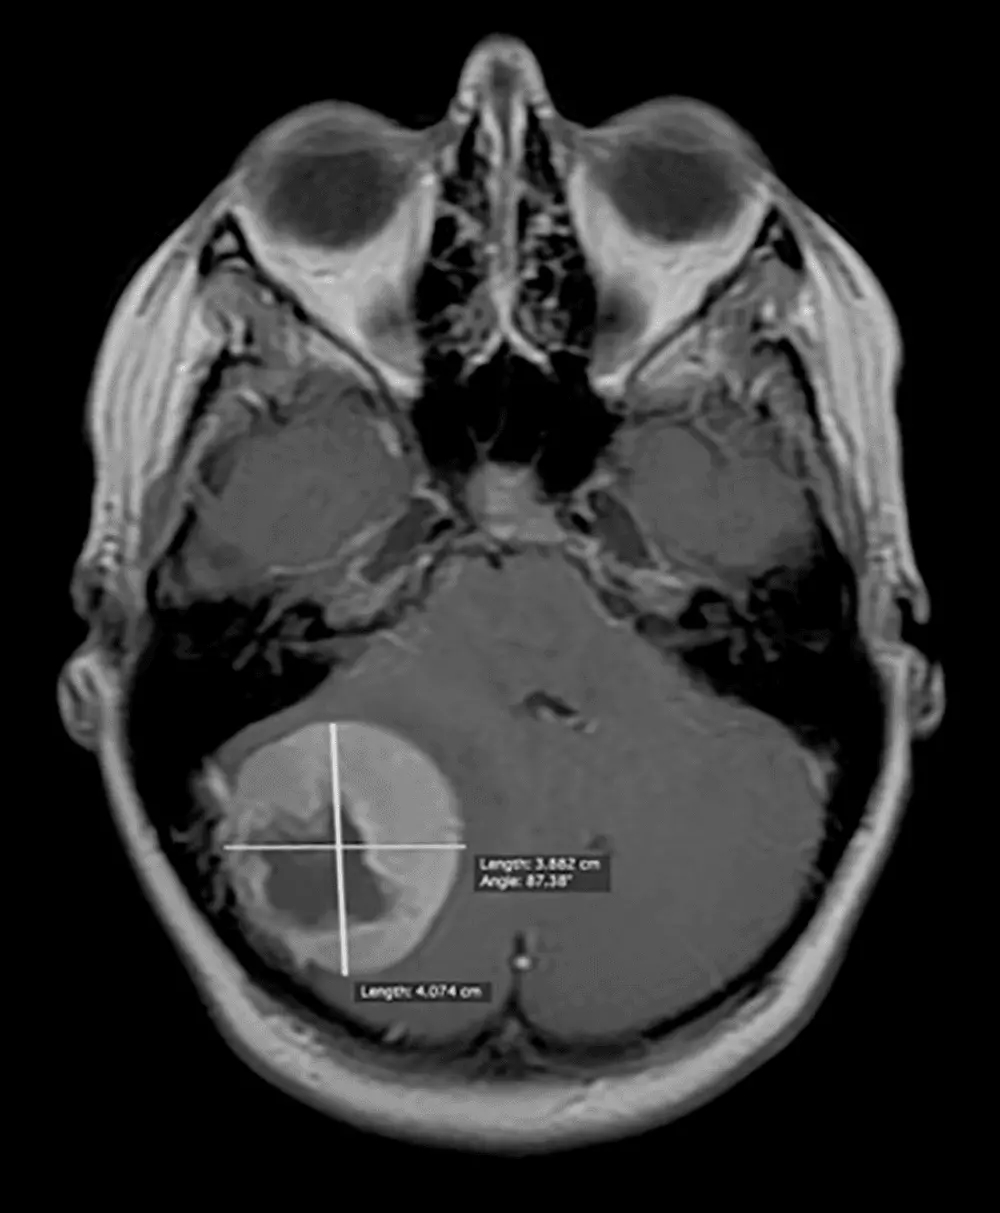

Przypadek kliniczny: 19-letnia pacjentka z oponiakiem tylnej jamy czaszki

Przypadek chorej M.D. lat 19, operowanej z powodu guza położonego podnamiotowo (w tylnej jamie czaszki), uciskającego w znacznym stopniu prawą półkulę móżdżku. Pomimo dużych rozmiarów guza jedynym objawem choroby był trwający od około roku ból głowy. Na podstawie wykonanych badań obrazowych – KT, następnie MR głowy, została zakwalifikowana do leczenia operacyjnego. Zmianę usunięto w całości, co potwierdzone zostało kontrolnym badaniem KT w drugiej dobie po operacji. Badanie histopatologiczne wykazało, że jest to oponiak w I stopniu złośliwości w klasyfikacji WHO. W przebiegu leczenia nie wystąpiły powikłania. Chorą wypisano do domu w stanie ogólnym i neurologicznym bardzo dobrym w czwartej dobie po zabiegu operacyjnym.